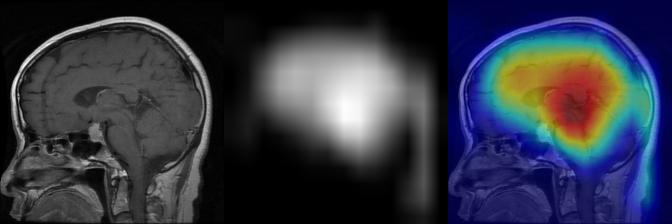

Explainable Brain Tumor Classification

GitHub Link